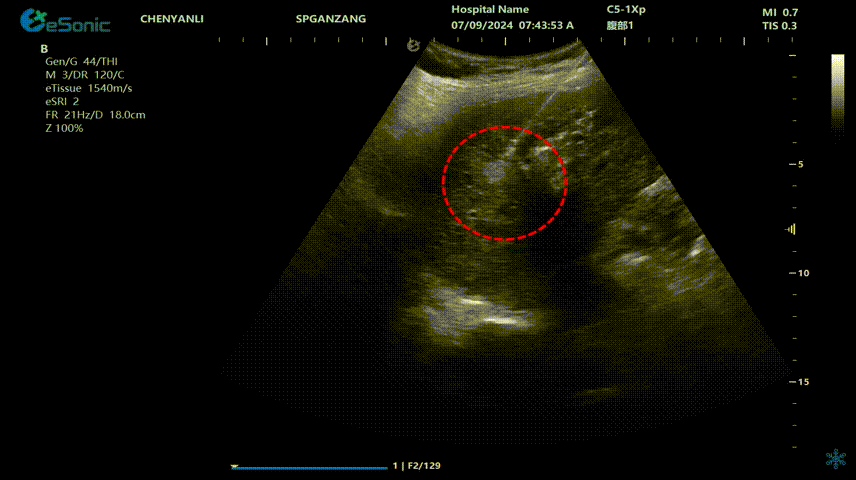

640 (1) (2).gif

肝癌射频消融动态视频

红圈为病灶位置

肝癌射频消融:全麻下彩超探头引导射频针分别植入肝右叶两个稍高回声结节,固定消融,至结节全部为强回声覆盖,覆盖良好,缓缓灼烧针道后退针。